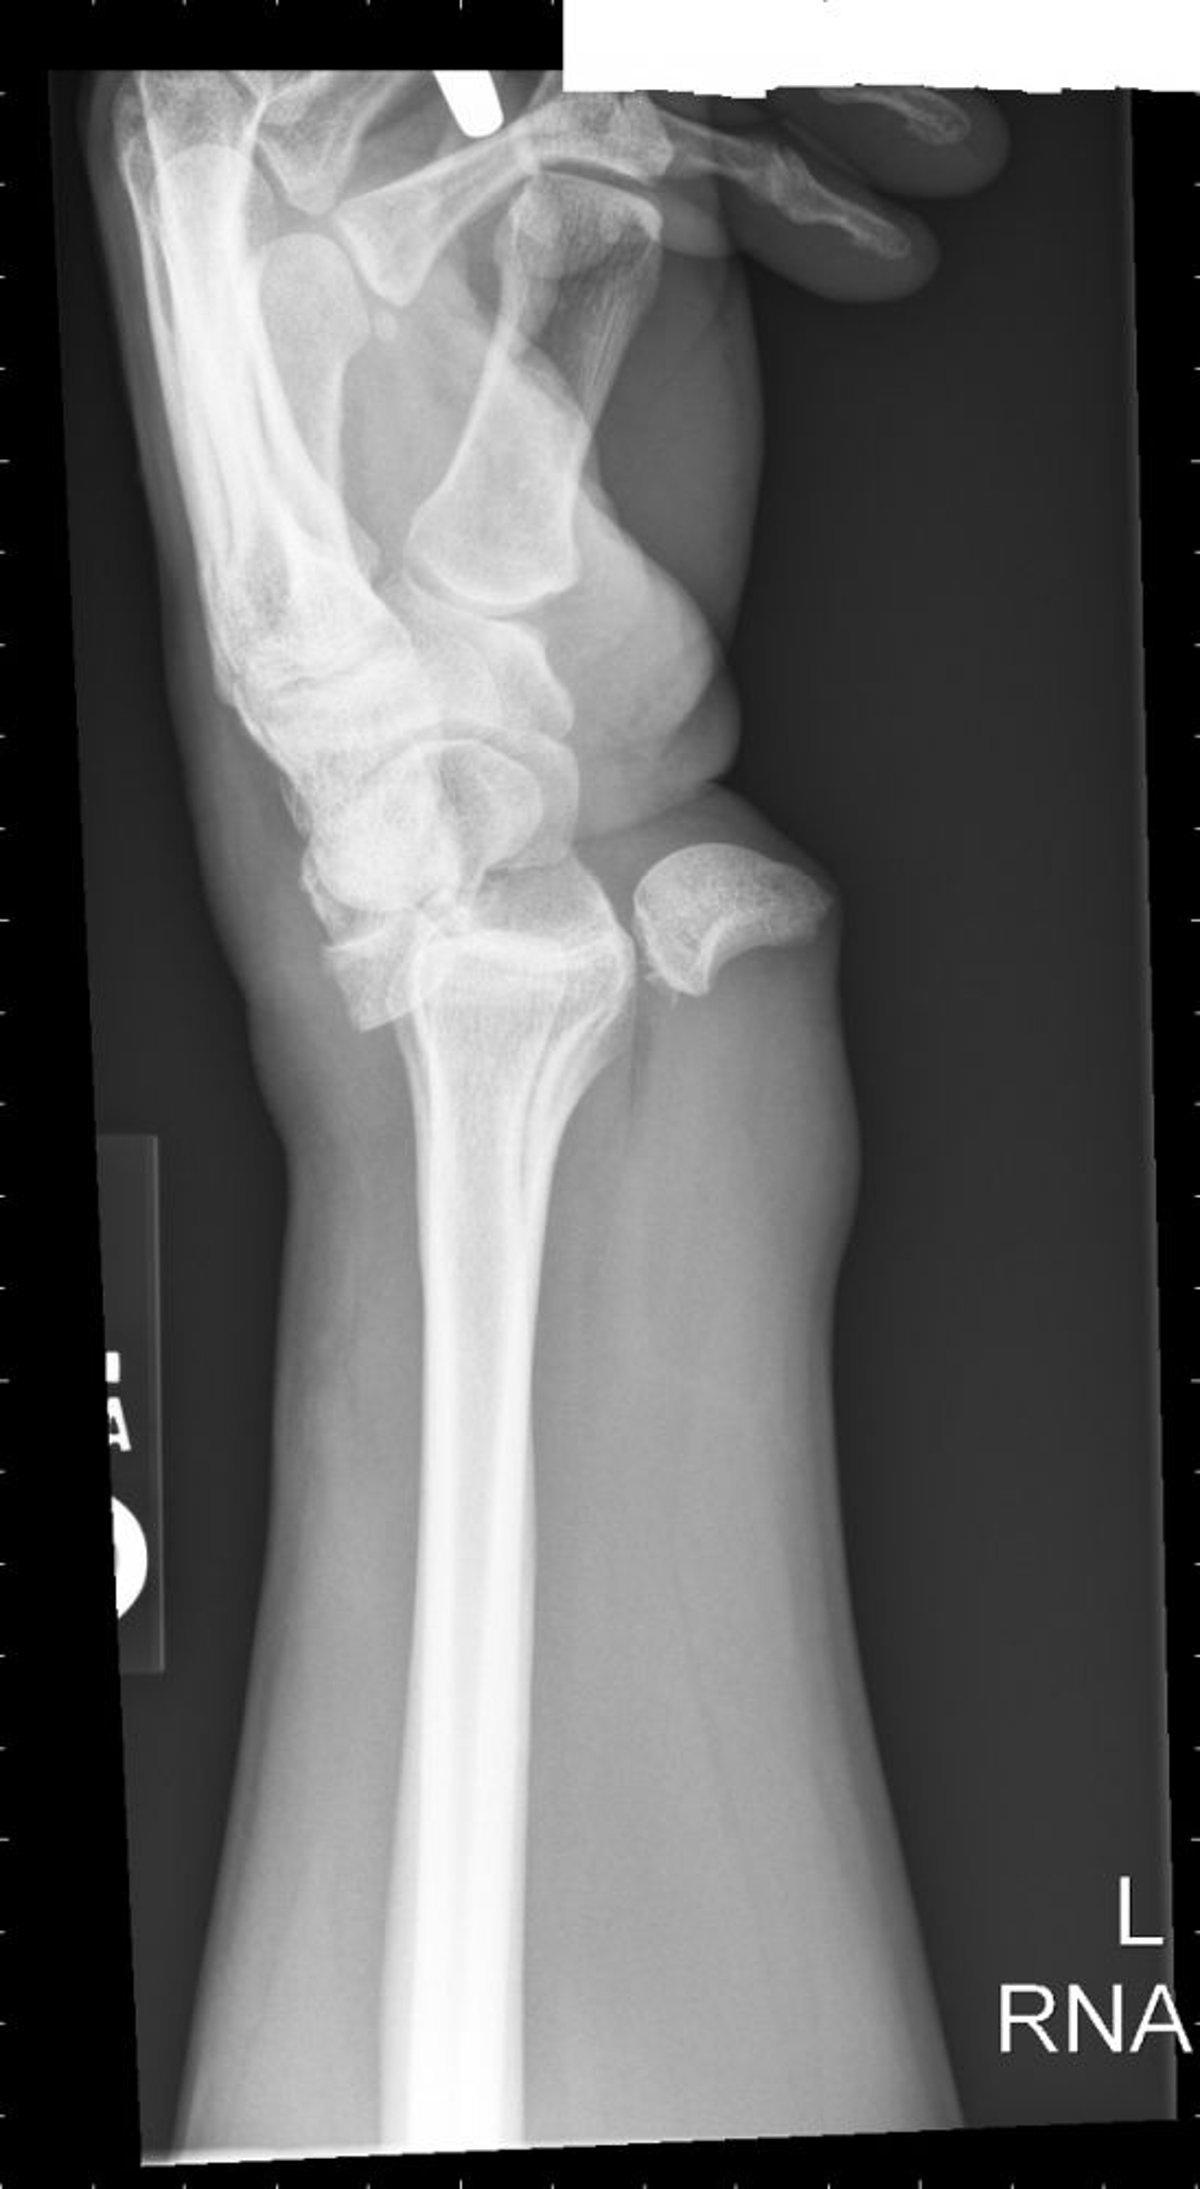

月状骨脱臼

月状骨脱臼では,こぼれたティーカップ状の配置(spilled teacup configuration)になる。

Image courtesy of Danielle Campagne, MD.